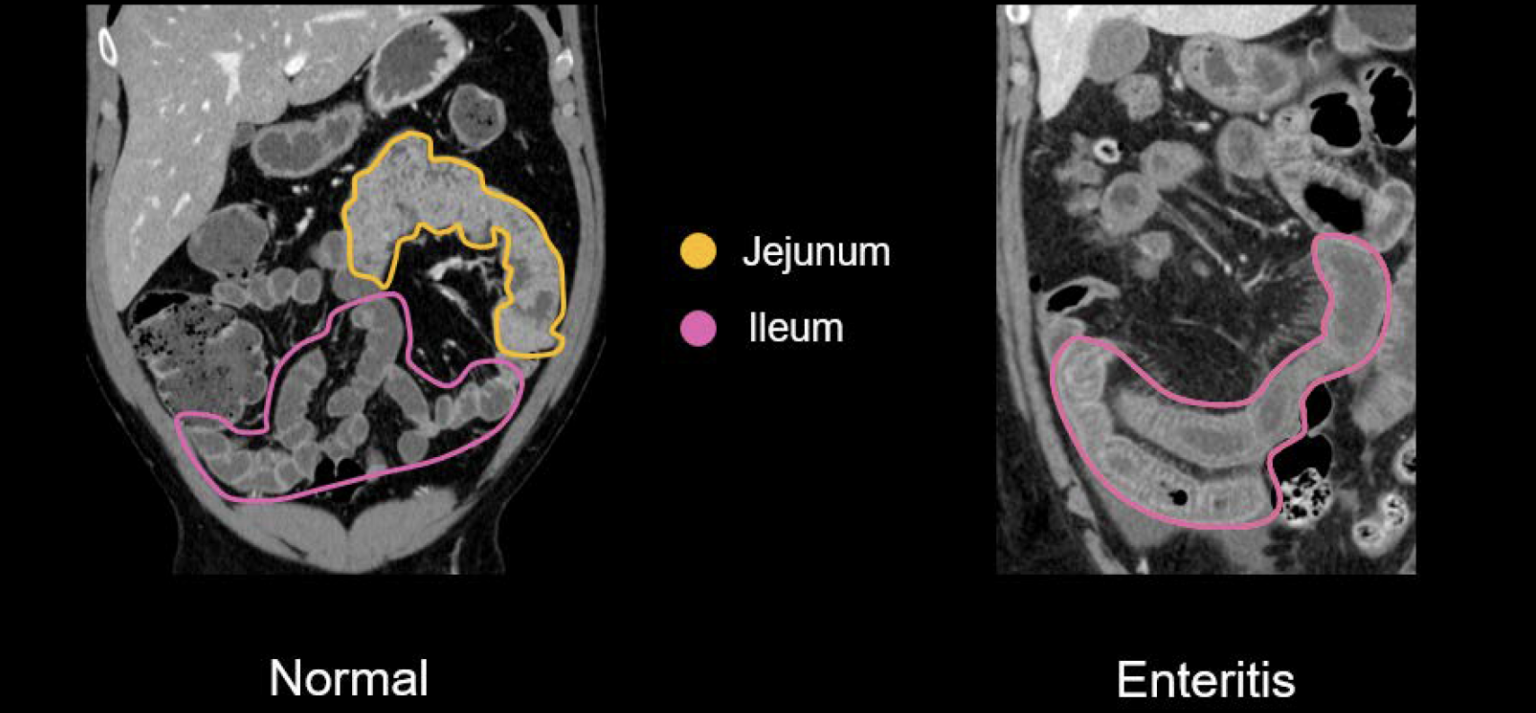

La localización de la enfermedad dependerá del campo de irradiación, aunque el sigma, el recto y el íleon terminal son segmentos afectadas con mayor frecuencia.

TAC

Los hallazgos en el TAC son similares a los de otras entidades inflamatorias, con engrosamiento concéntrico de la pared, en ocasiones con halo hipodenso intramular y aumento en la densidad de la grasa del mesenterio. Cuando existe confluencia de asas intestinales, adheridas y con la pared engrosada, puede simular una recidiva neoplásica.